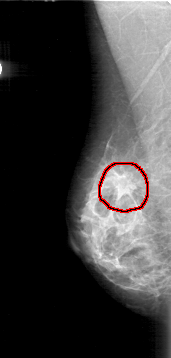

D_4185_1.RIGHT_MLO

FILE: D_4185_1.RIGHT_MLO.OVERLAY

TOTAL_ABNORMALITIES 1

ABNORMALITY 1

LESION_TYPE MASS SHAPE IRREGULAR MARGINS SPICULATED

ASSESSMENT 5

SUBTLETY 4

PATHOLOGY MALIGNANT

TOTAL_OUTLINES 1

BOUNDARY